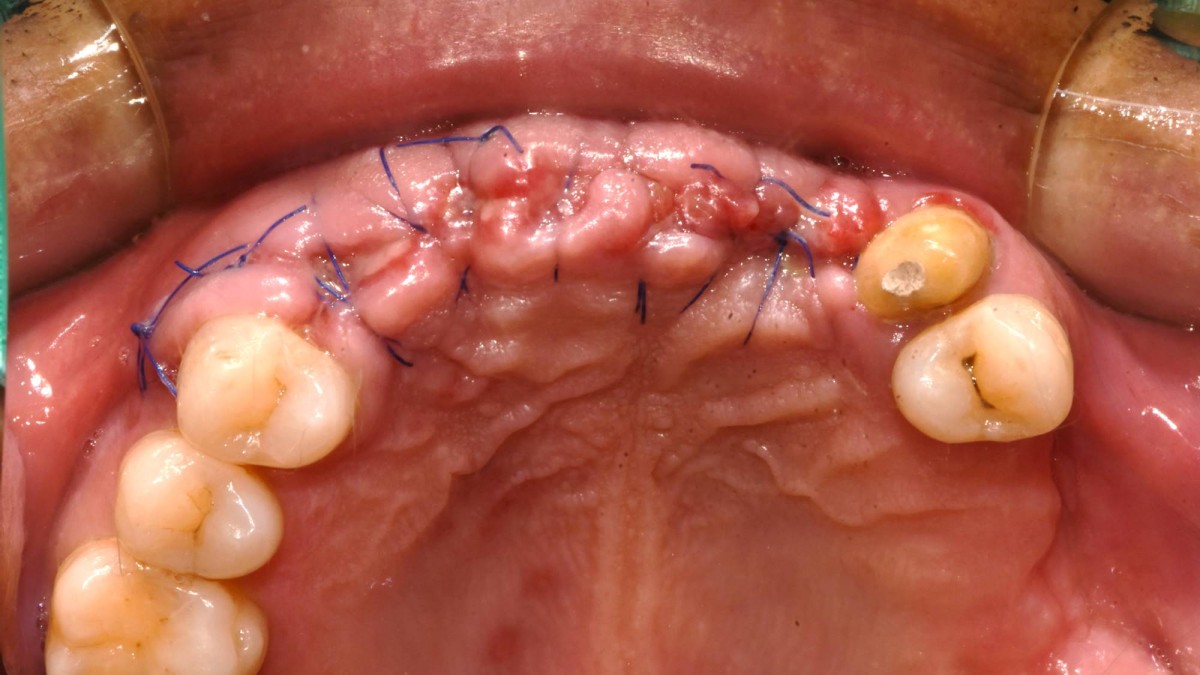

In the anterior maxilla, implant-supported fixed partial denture.

<GCpbc> A 58-year-old male is a patient undergoing implant installation in various parts. The old Br of the anterior maxilla has fallen

off and it is no longer possible to maintain it even temporarily, so a

treatment plan for the anterior teeth was made.